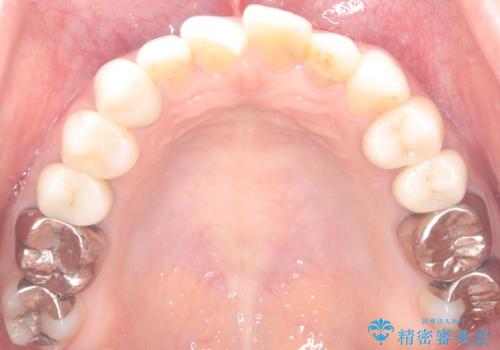

外れ欠けている土台をまずやり替えた後、根管治療後の緊密な封鎖を目的としオールセラミッククラウンをセットしました。

・仮歯:10,000円(税抜き)

・ファイバ-コア(土台):20,000円(税抜き)

・オールセラミッククラウン(スタンダード):110,000円(税抜き)